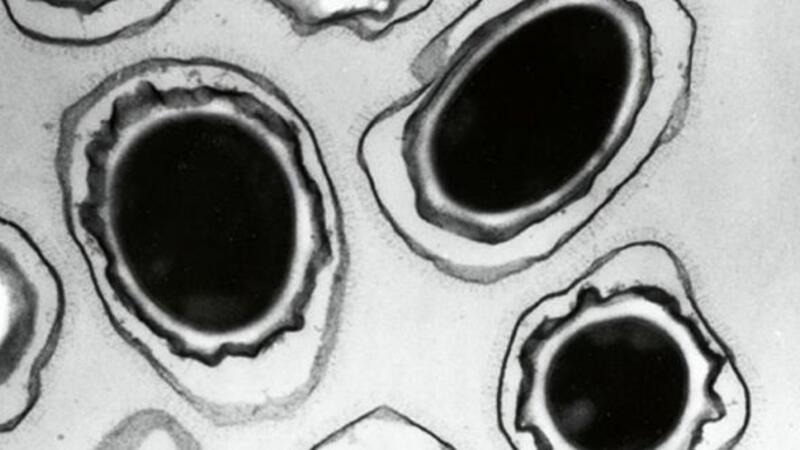

A microscopic view of anthrax spores. Photograph (AFP)